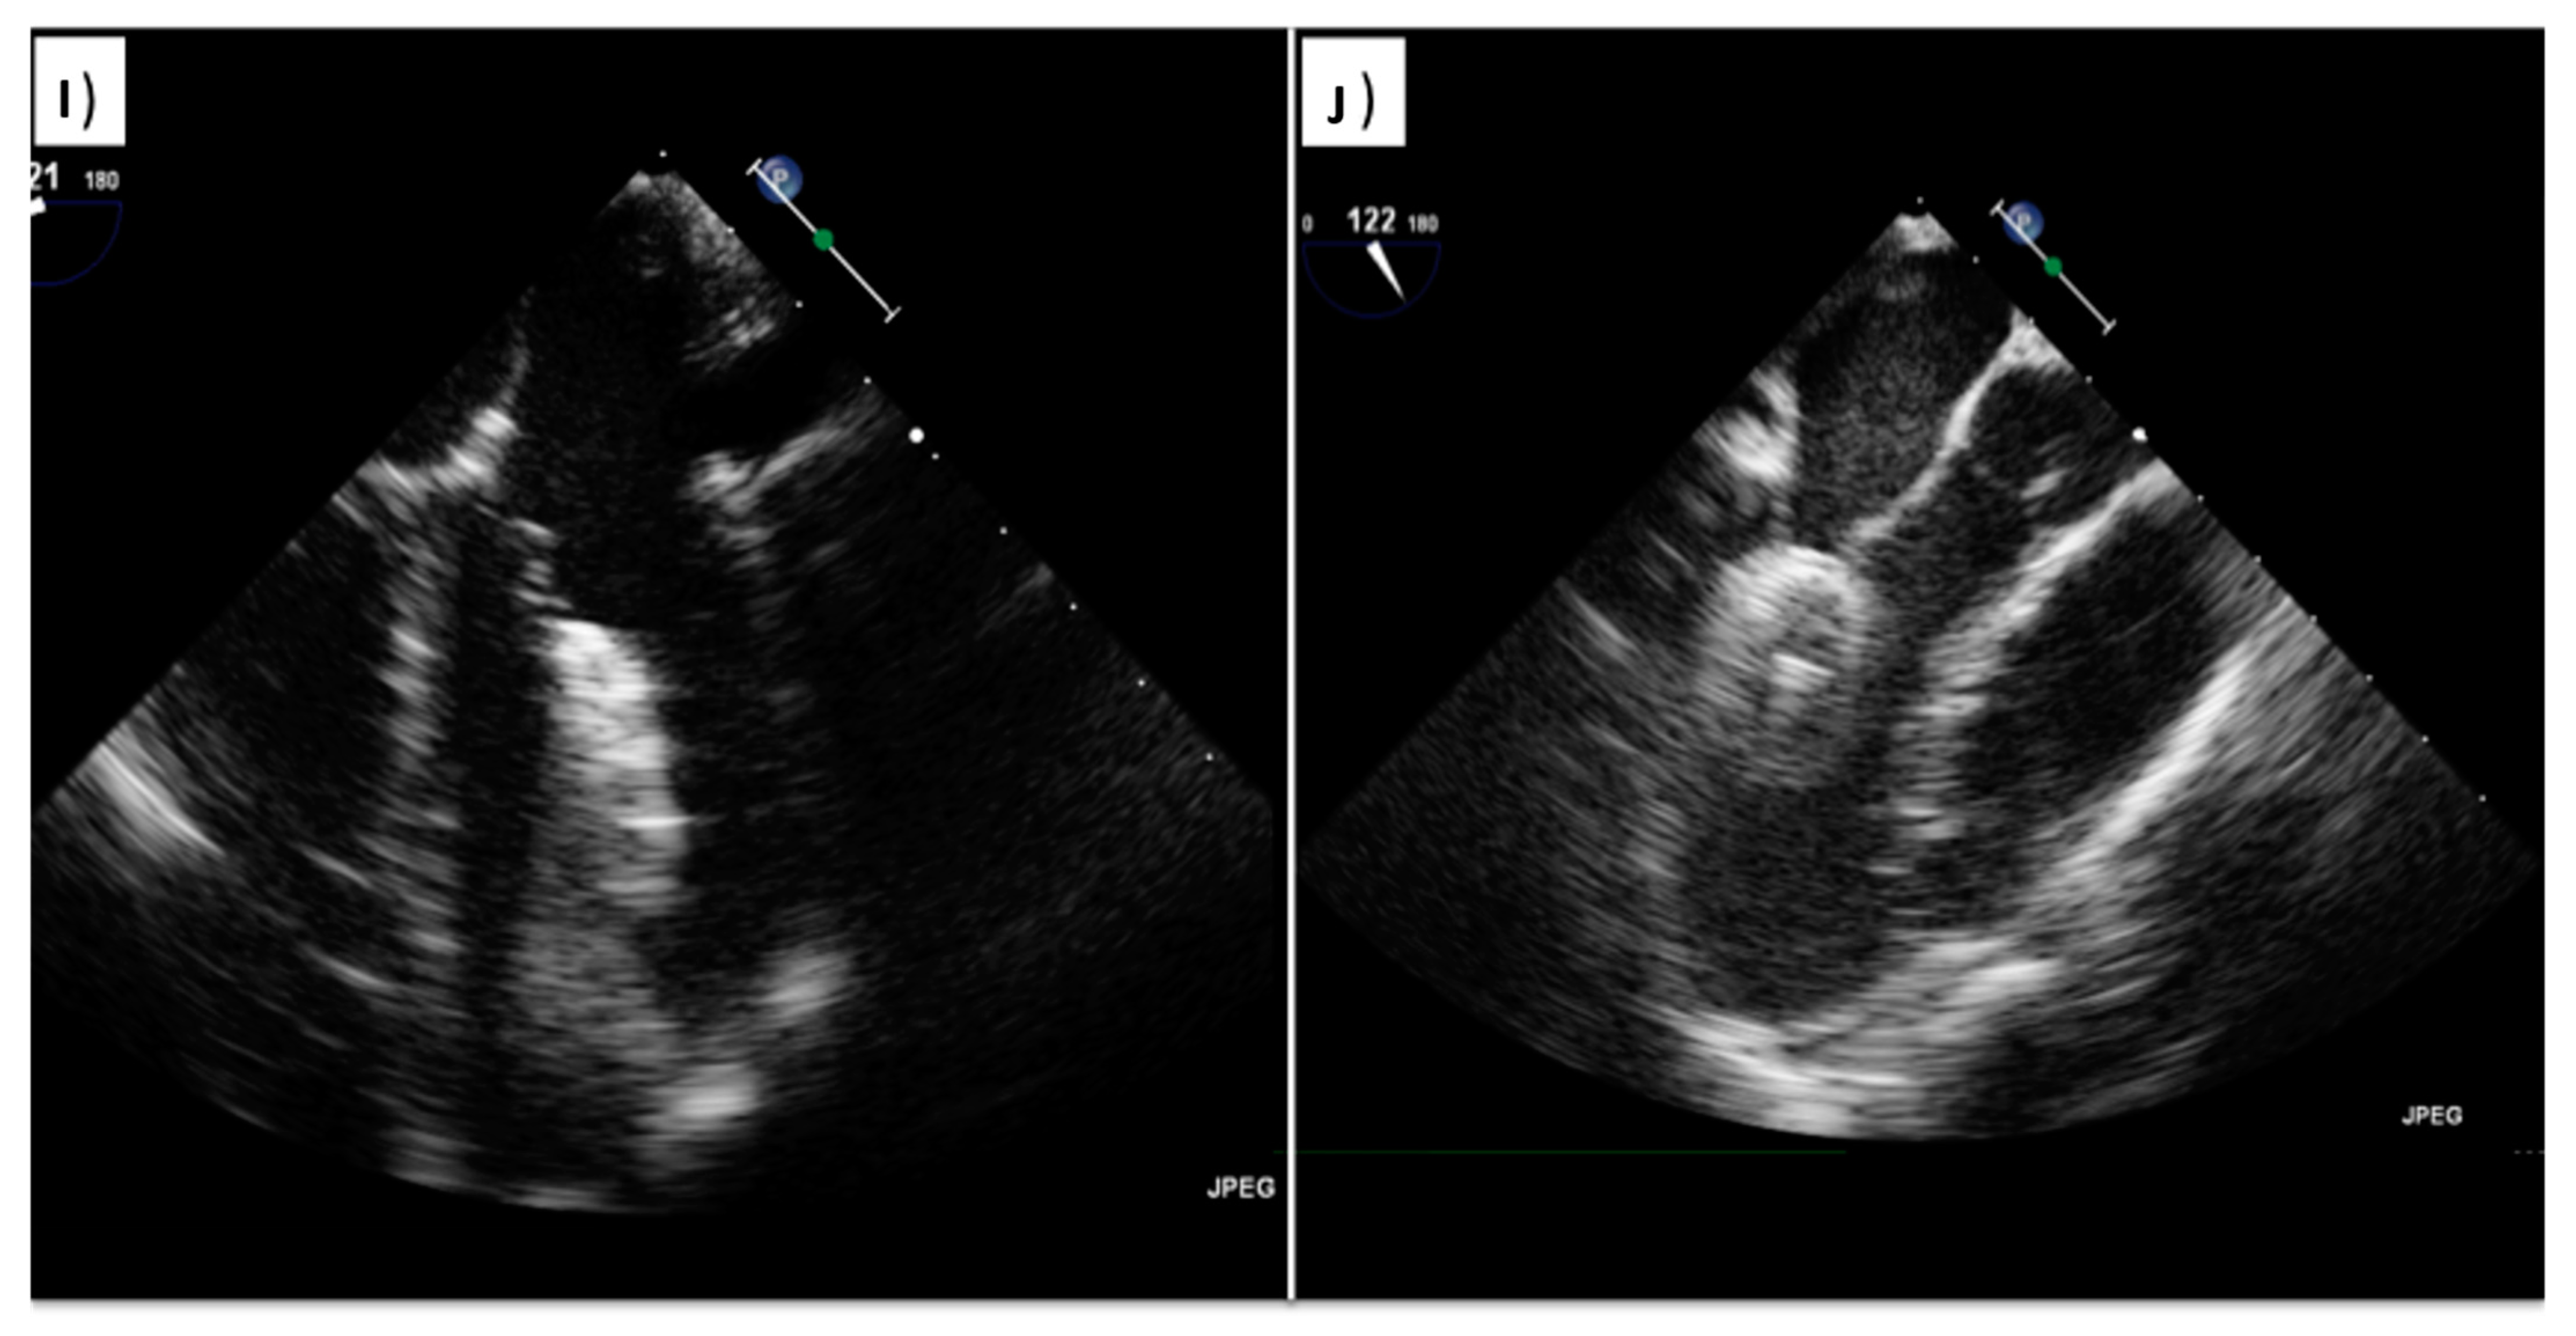

Atrial Septal Defect Closure Using 3d Transesophageal vrogue.co Asd Closure Device Radiology this review summarizes the specific role of different imaging modalities for pfo and asd transcatheter closure,. closure of an atrial septal defect (asd) is done surgically or, in select patients with a secundum asd, via a percutaneous device. By far the most common type of asd is the secundum type, comprising 70% to 80% of all asds. . Asd Closure Device Radiology.

JCDD Free FullText Transcatheter Closure of PFO and ASD Asd Closure Device Radiology By far the most common type of asd is the secundum type, comprising 70% to 80% of all asds. atrial septal defect (asd) devices are typically below a line drawn from the carina to the cardiac apex in a lateral radiograph. For most individual patients with suitable. This type of defect occurs when there is failure. closure of. Asd Closure Device Radiology.